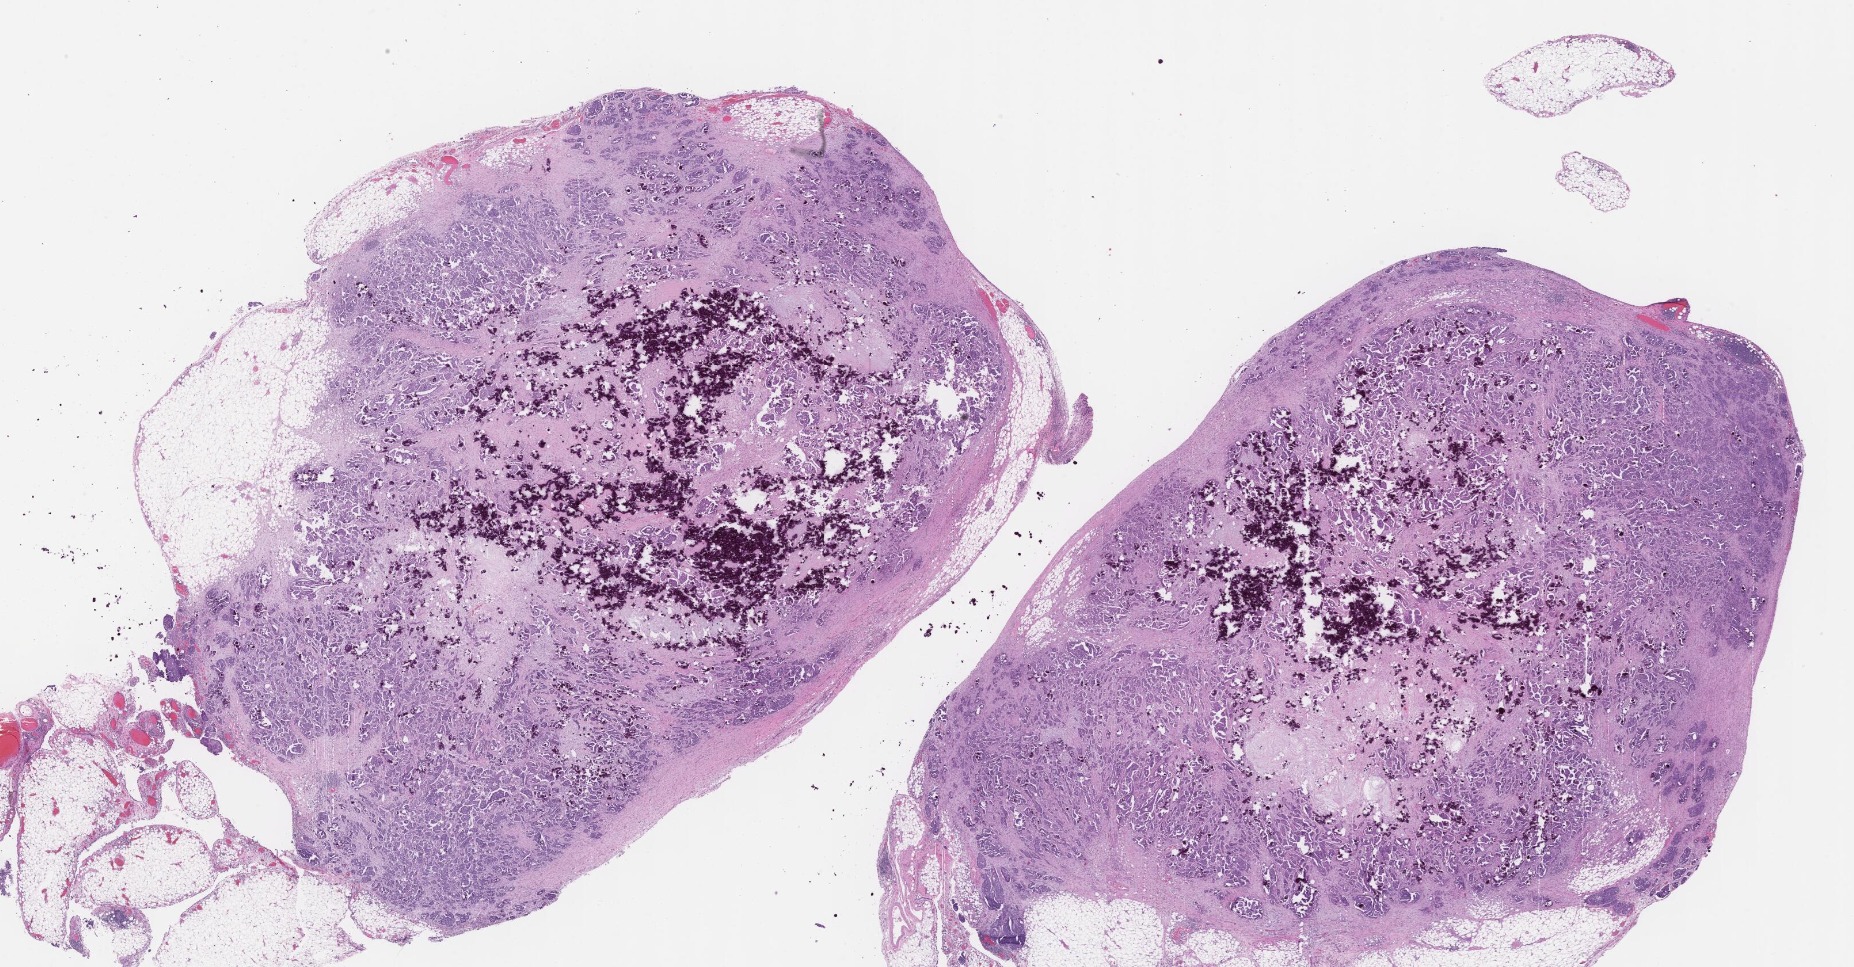

We process images of all kinds. As for medical imaging both structural and functional modalities like MRI, CT, PET, UH and X-ray are supported. Microscopy imaging for laboratory purposes offered in our portfolio include histopathology (H&E, IHC), cytology (e.g. pap smear), blood smear, cell culture and fertility/IVF. Regarding research we create solutions for brightfield and fluorescent microscopy, high-content screening, pharmaceutical testing, bacteria colony counting etc.

Handling large amounts of imaging data is carefully performed by developing software tools that smoothly fit into the workflow to accelerate scientific progress, discovery or diagnosis. Applying cutting-edge AI-driven approaches to process data we offer reliable and accurate quantitative analysis from raw input to conclusions whether for detection, classification, segmentation or tracking. We help the experts find tumours, anomalies, cellular response and insight with a personalized and supportive solution.